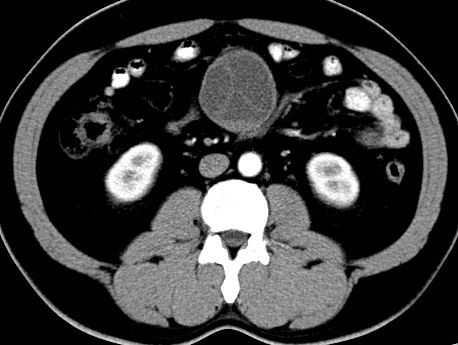

(腹腔)神经鞘瘤

男,48岁,间断性下腹不适1年。

手术探查

:距回盲部28厘米处肠系膜根部可见5*7cm左右包块,质中等硬度,活动度尚可,肝、胆、胰、脾肾未见明显异常。

病理

:(腹腔)

神经鞘瘤

,伴出血、坏死及囊性变,伴淋巴结反应性增生。

免疫组化结果

:sma(-), desmin(-), cd117(-), s-100(+++), nf(-),vimentin(+++).